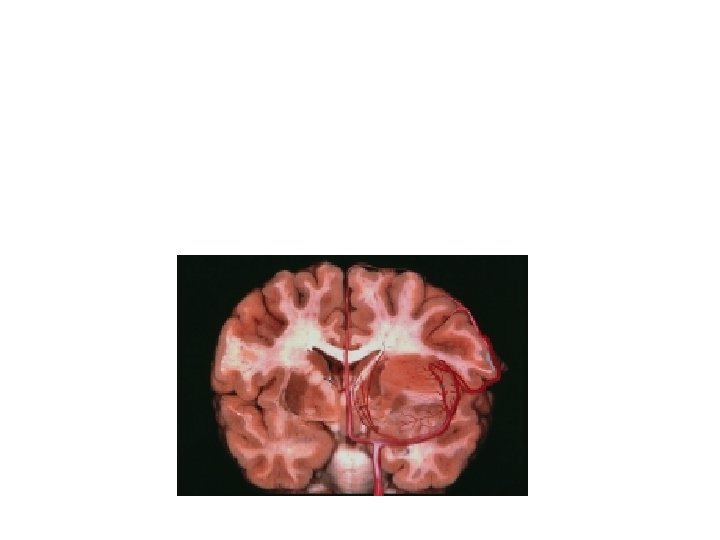

Tumor LSAs medial displacement Open biopsy: anaplastic glioma Anaplastic Astrocytoma: atypia, ipercellularity and mitosis (WHO III)